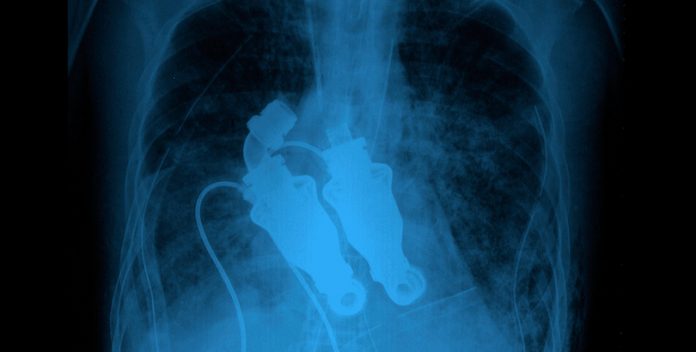

Cohn y Frazier tenían un ternero de 8 meses dentro de su laboratorio de investigación, al que llamaban Aba. Para su experimento, sustituyeron el corazón de Aba por dos bombas centrífugas; al escuchar su pecho a través de un estetoscopio, no pudieron oír los latidos de su corazón.

El animal siguió con vida, moviéndose, comiendo y durmiendo. Las bombas hacían girar la sangre y la movían por todo el cuerpo de Aba. Con el propósito de demostrar que el dispositivo podía funcionar en humanos, los doctores siguieron sus pruebas con más terneros.

Con gran éxito, el procedimiento tardó menos de 48 horas y Craig Lewis se convirtió en el primer hombre en recibir esta tecnología. Lewis podía sentarse en una silla y hablar, lo que ya representaba un gran logro. Sin embargo, con el transcurso de las semanas, comenzó a desvanecerse, pues la enfermedad atacó también al hígado y riñones.